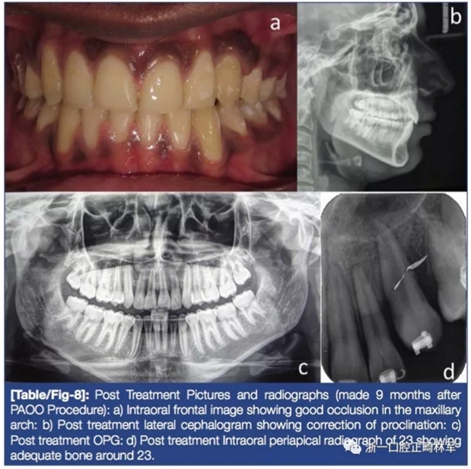

術(shù)后,糾正23旋轉(zhuǎn)(圖6)。有較大旋轉(zhuǎn)量后換用0.017×0.025-in銅鎳鈦絲將23排入牙弓,45天后完成(圖7)。最后階段關(guān)閉間隙,治療結(jié)束(圖8)。保持階段上頜使用Begg環(huán)繞式保持器,下頜使用固定保持器。

5年后隨訪結(jié)果:除了23有輕微的近中腭向旋轉(zhuǎn)外,余均保持穩(wěn)定(圖9)。

在多種加速治療法中,骨皮質(zhì)切開術(shù)由于其有效性較受歡迎。其基于“局部加速現(xiàn)象(RAP)”,即在骨損傷處有一個(gè)快速的改建和愈合。骨皮質(zhì)切開附近由于骨的快速改建阻力減小牙齒移動(dòng)更快。研究表面骨皮質(zhì)切開術(shù)能在不影響牙周組織的前提下減少正畸治療時(shí)間。目前尚無文獻(xiàn)證明使用PAOO術(shù)增加骨水平。本病例中,整個(gè)矯正23的PAOO階段為45天,不包括間隙關(guān)閉,剩余調(diào)整的治療時(shí)間為9個(gè)月。除了能加快牙齒移動(dòng)外,PAOO的優(yōu)勢(shì)還有減少牙根吸收及保持牙髓活力。病例顯示PAOO術(shù)后結(jié)果穩(wěn)定。